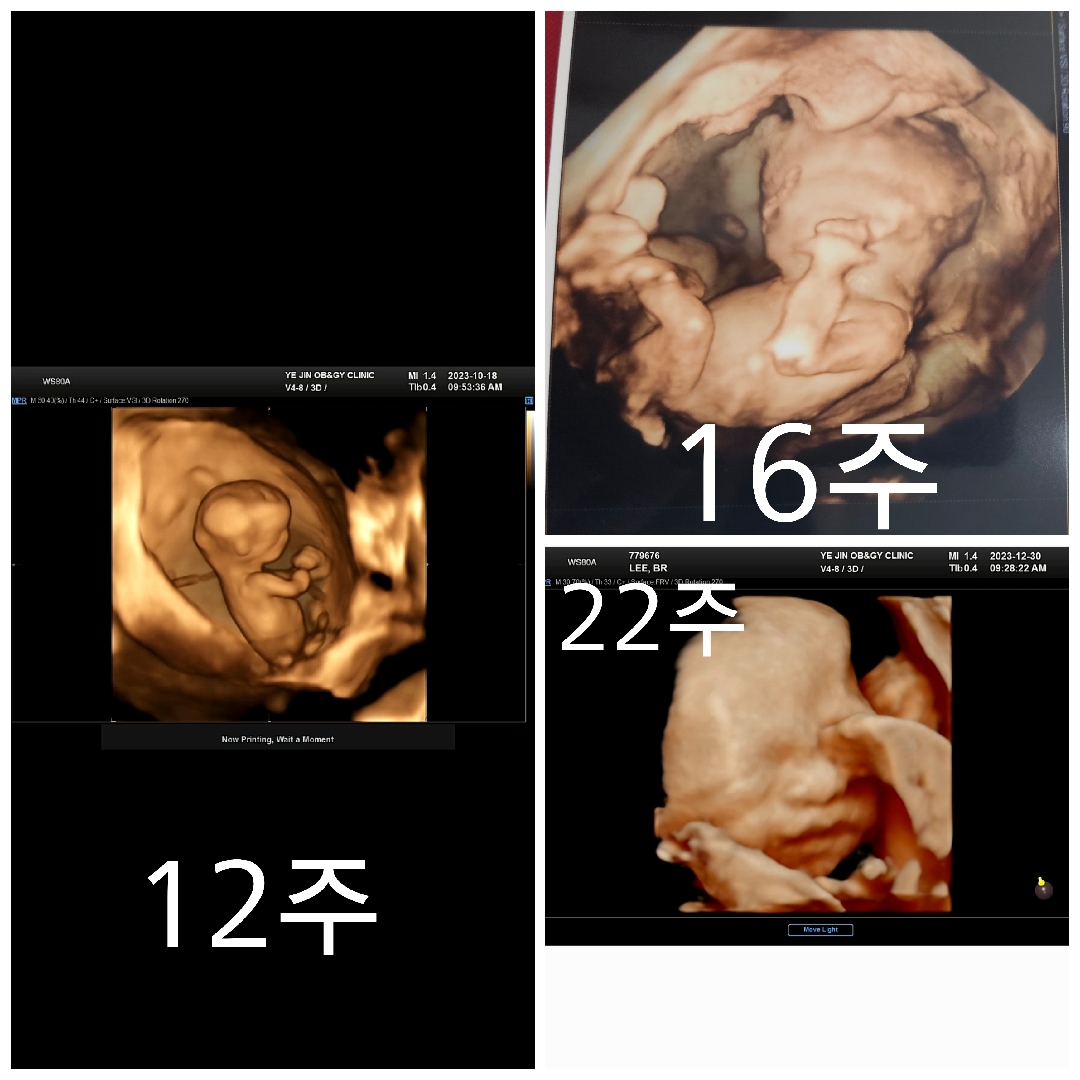

입체 초음파 찍어놓은거 모아보니까 진짜 많이 컸네요~

이렇게 모아놓고 보니까 진짜 많이 컸네요~ㅎㅎ우리 아들 다음에 임당검사 때 만날 때는 더 커있겠지??ㅎㅎ